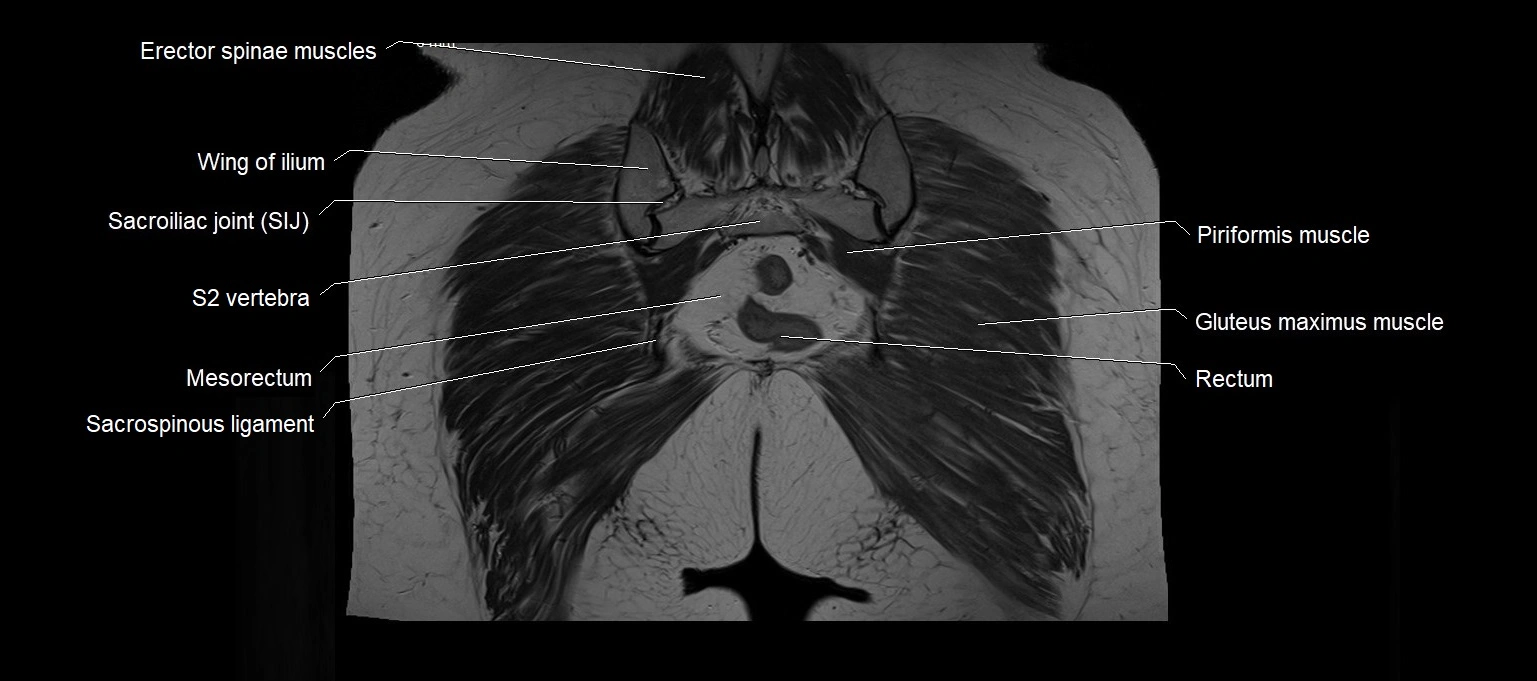

MRI images